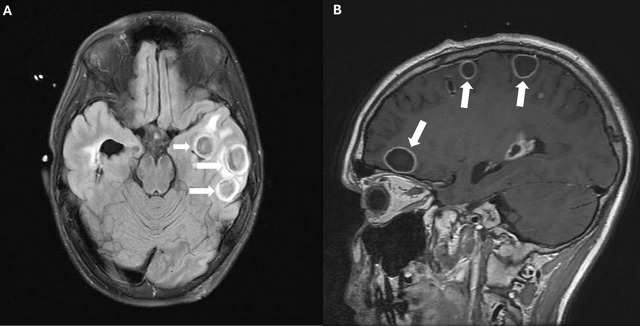

Case presentation: A 12-year-old adolescent male who had headache and photophobia and was diagnosed with multiple brain abscesses and was refractory to conventional medical and neurosurgical intervention. A single dose of 10 mg vancomycin was administered through endo-ventricular drain, resulting in resolution of abscesses and alleviation of symptoms.